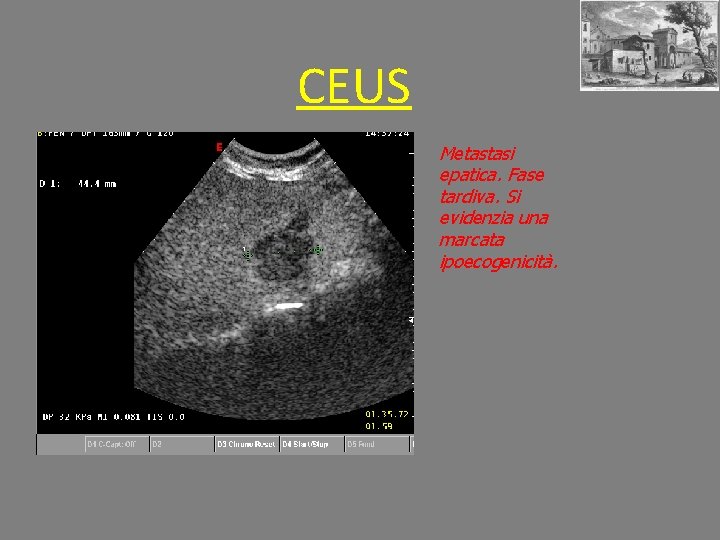

CEUS Metastasi epatica. Fase tardiva. Si evidenzia una marcata ipoecogenicità.